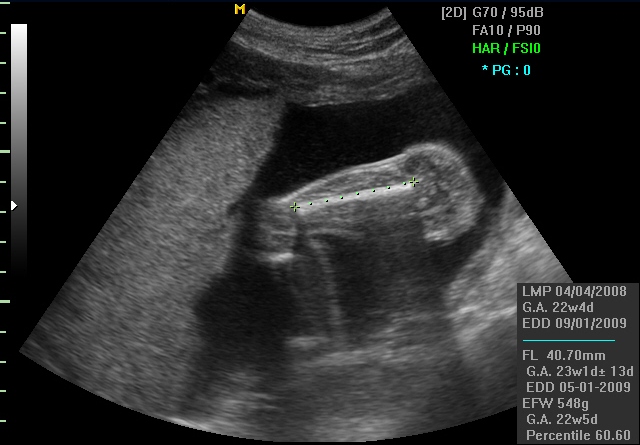

FL (Femur length) ја претставува должината на бутната коска, најдолгата коска во телото на бебето. На овој начин се следи растот на бебето во должина.